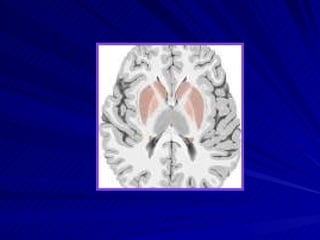

Parts of basal ganglia

The brain structures that comprise The Basal Ganglia  Putamen,  Caudate nucleus,  Globus pallidus  Substantia nigra  Subthalamic nucleus of Luys

The brain structuresthat comprise The Basal Ganglia Putamen, Caudate nucleus, Globus pallidus Substantia nigra Subthalamic nucleus of Luys